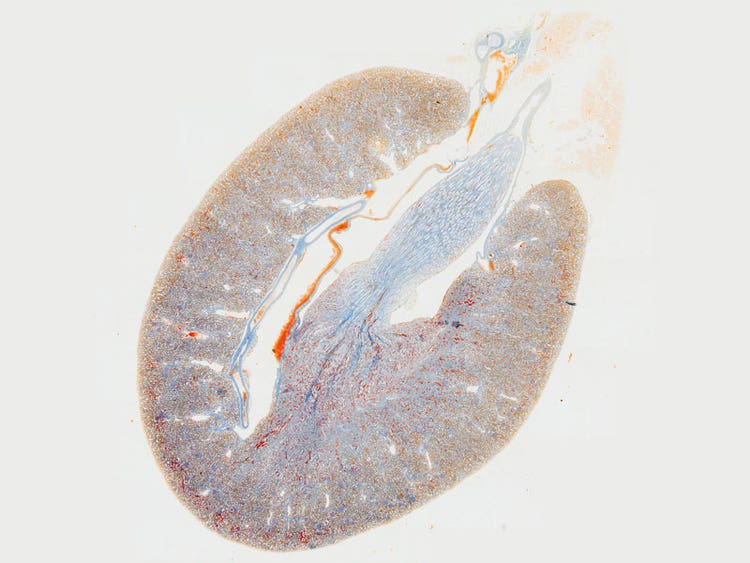

La aplicación «mosaico» le permite generar imágenes de secciones tisulares completas; sin embargo, si la planitud de la imagen es insuficiente, la imagen en mosaico puede parecer borrosa y presentar una combinación dispar. Los objetivos de la X Line proporcionan imágenes planas uniformes desde el centro hasta el borde, lo que le permite adquirir imágenes en mosaico uniformes y de alta definición. También puede crear una gran imagen en mosaico usando menos imágenes que antes para mejorar su eficacia y ahorrar tiempo.

Imagen creada con la función de alineación de múltiples imágenes (AMI)